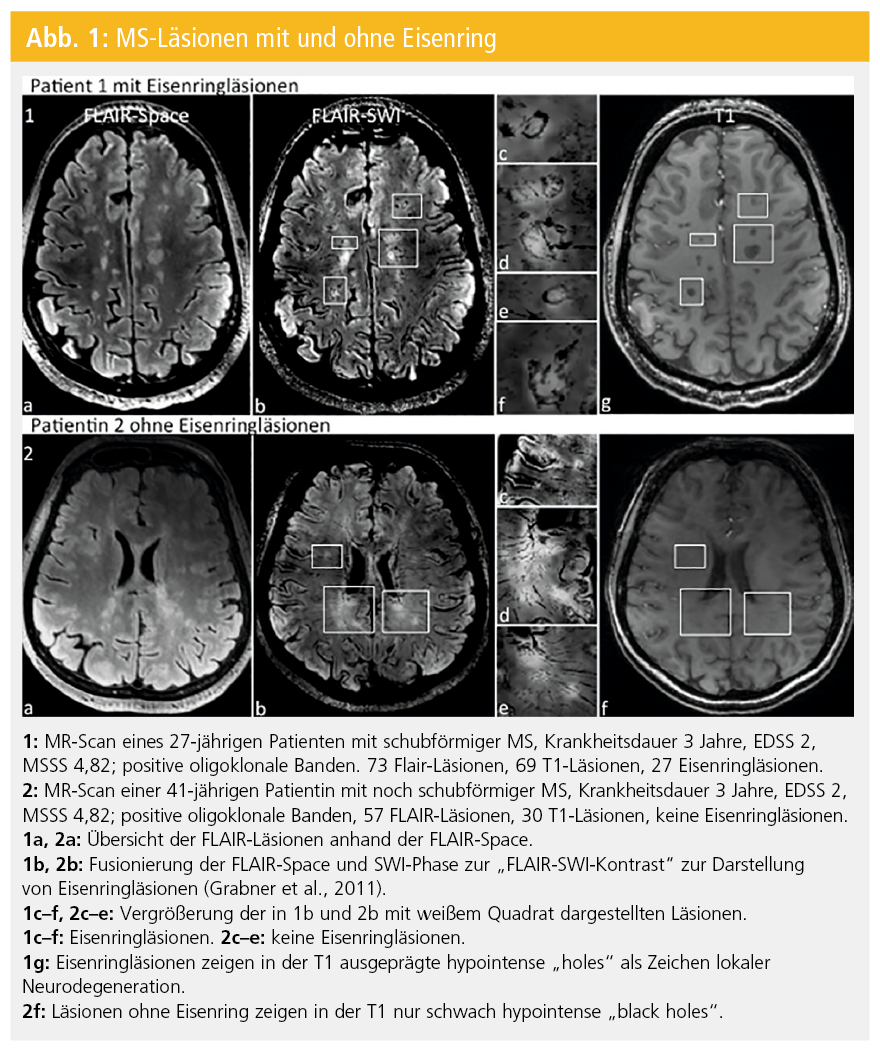

Die magnetresonanztomografie (mrt) hat in vielfältiger weise zum verständnis der ms beigetragen.